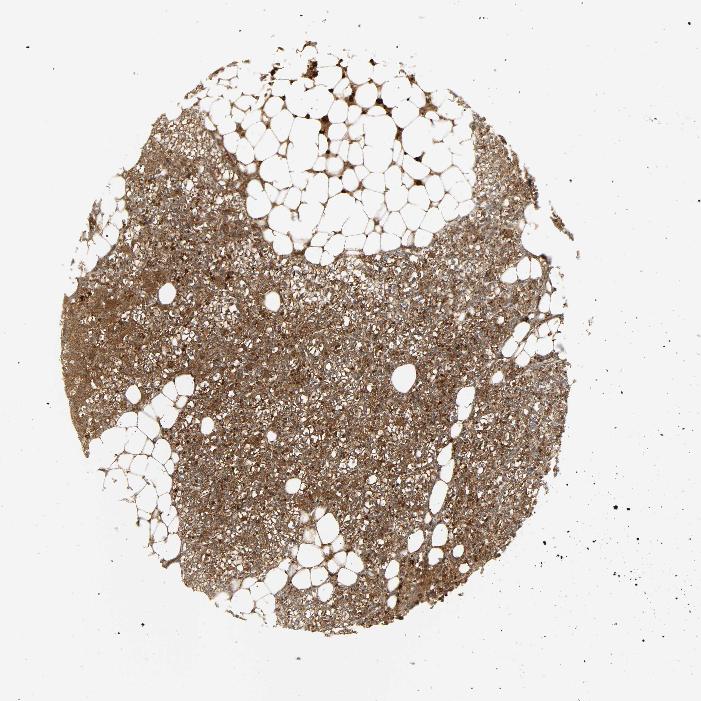

TISSUE PRIMARY DATA PARATHYROID GLAND Show tissue menu

PARATHYROID GLAND - Antibody stainingi

Antibody staining in the annotated cell types in the current human tissue is reported as not detected, low, medium, or high, based on conventional immunohistochemistry profiling in selected tissues. This score is based on the combination of the staining intensity and fraction of stained cells.

Each image is clickable and will lead to virtual microscopy that enables deeper exploration of all samples and also displays staining intensity scores, fraction scores and subcellular localization as well as patient and tissue information for each sample.

Antibody HPA001402Antibody CAB004240Antibody CAB018564

Glandular cells MediumHighMedium